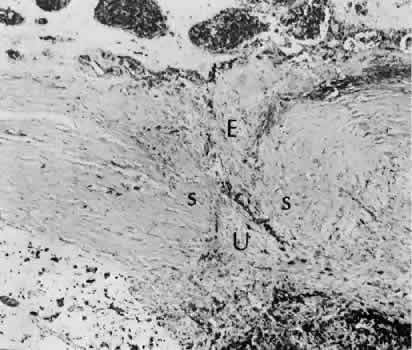

SCLERAL HEALING

The sclera itself does not participate directly in wound healing. Partial-thickness injuries are healed by formation of granulation tissue from the epi-scleral tissue in external wounds or from uveal tissue in internal wounds (Fig. 8). Full-thickness defects of the sclera heal by granulation tissue originating in the episcleral tissue and uveal tract. Mitomycin is used in filtering procedures specifically to prevent the formation of granulation tissue and promote establishment of an aqueous fistula.30

Fig. 8. Following a scleral incision, granulation tissue from episcleral tissue (E) and uveal tissue (U) will proliferate through the full extent of the sclera. The tissue will remodel along tension lines to reapproximate the tensile strength of the original tissue (Hematoxylin-eosin stain; × 28.)